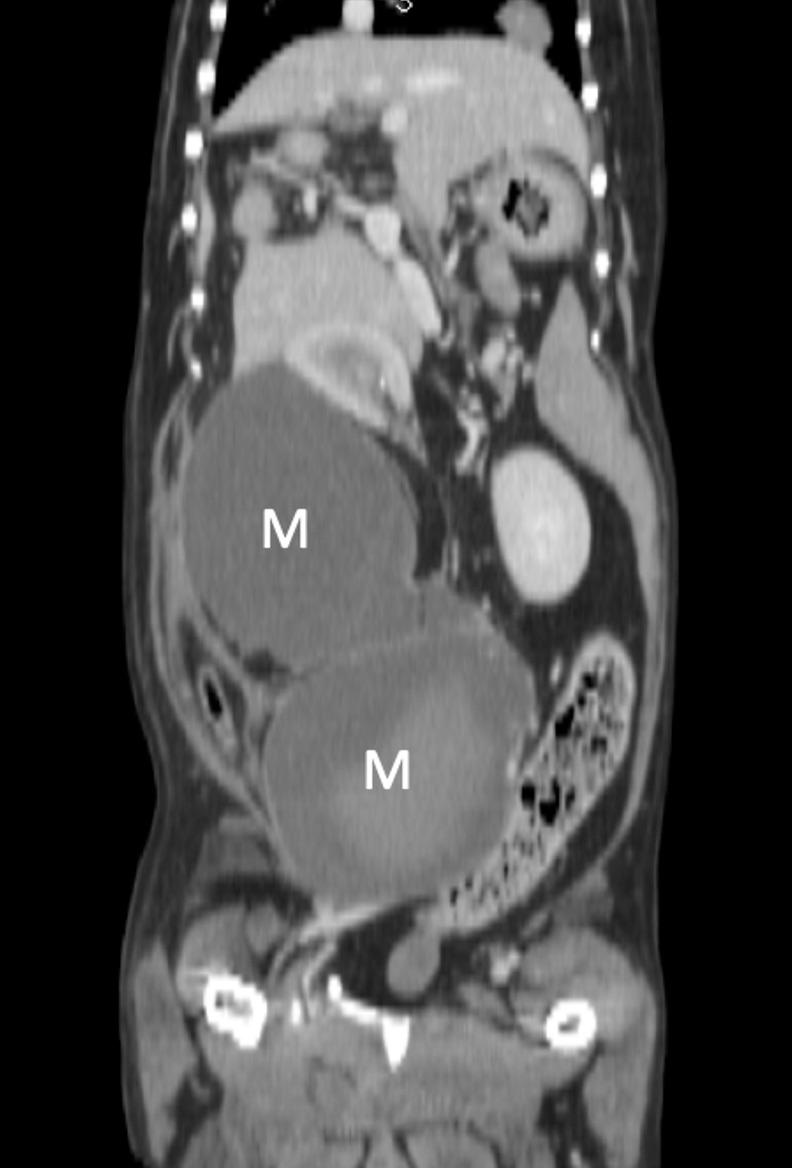

本コラムでは獣医療の専門的な情報を取り扱っており、手術中の写真など刺激を受ける可能性のある医療画像を含む場合があります。